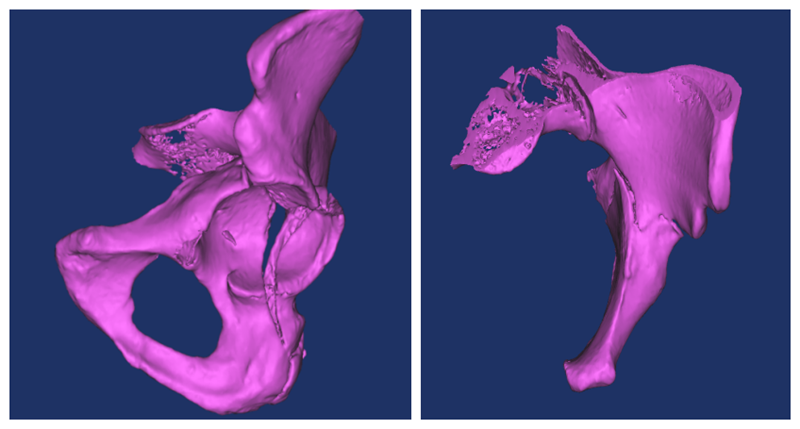

我们应用软件自动建立虚拟骨盆三维仿真模型,应用相关软件功能模块建立虚拟圆柱体替代拉力螺钉,将虚拟圆柱体置入髋臼前柱骨质内,逐渐增大虚拟圆柱体的直径直至髋臼前柱骨质边缘,在三维层面中记录虚拟圆柱体的直径及长度,并测量入钉点与相关髋臼解剖结构的距离,测量虚拟圆柱体的入钉角度及螺钉在骨盆正位、入口位与骨盆正中线的夹角。在得到精准的螺钉入点、长度、角度等测量值后,为术中置钉提供了较为重要的参考价值。

(进行图像分割后获得骨盆髋臼,模拟髂骨斜位与骨盆入口位)

(术前模拟规划前柱通道螺钉入点与角度)